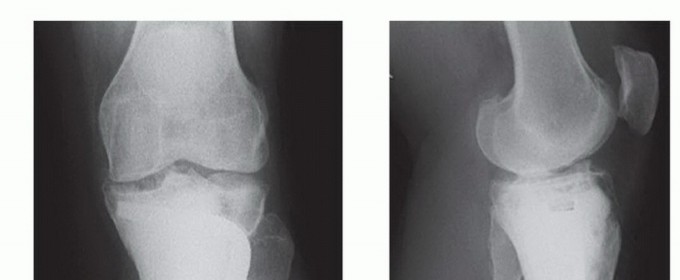

يُعد العلاج بالتبريد، خاصةً بتقنية الصب المباشر بالنيتروجين السائل، ثورة حقيقية في علاج أورام العظام، حيث يقدم بديلاً فعالاً وآمنًا للجراحات الكبرى، مع الحفاظ على الطرف المصاب ووظيفته. يعتمد هذا النهج على تدمير الخلايا السرطانية عن طريق تعريضها لدرجات حرارة منخفضة جدًا، مما يؤدي إلى تجميدها وموتها.

تتمثل الفكرة الأساسية في تجميد الخلايا السرطانية وتذويبها بشكل متكرر. عند تجميد الخلايا، تتكون بلورات الثلج داخل وخارج الخلايا، مما يؤدي إلى:

* تمزق أغشية الخلايا: بلورات الثلج الحادة تمزق الجدران الخلوية.

* تلف العضيات الداخلية: تدمير الميتوكونندريا وغيرها من العضيات الحيوية.

* خلل في التوازن الكيميائي: اضطراب في تركيز الأملاح داخل وخارج الخلية.

* انسداد الأوعية الدموية: تدمير الأوعية الدموية الدقيقة التي تغذي الورم، مما يؤدي إلى نقص الأكسجين والمغذيات وموت الخلايا.

* الاستجابة المناعية: قد يحفز العلاج بالتبريد استجابة مناعية ضد الخلايا السرطانية المتبقية.

دواعٍ استخدام العلاج بالتبريد

- أورام العظام الحميدة: مثل الورم العظمي العظمي (Osteoid Osteoma)، الورم الغضروفي العظمي (Osteochondroma)، أكياس العظام.

- أورام العظام الخبيثة الأولية: في بعض الحالات المختارة، خاصة في المراحل المبكرة أو الأورام الصغيرة.